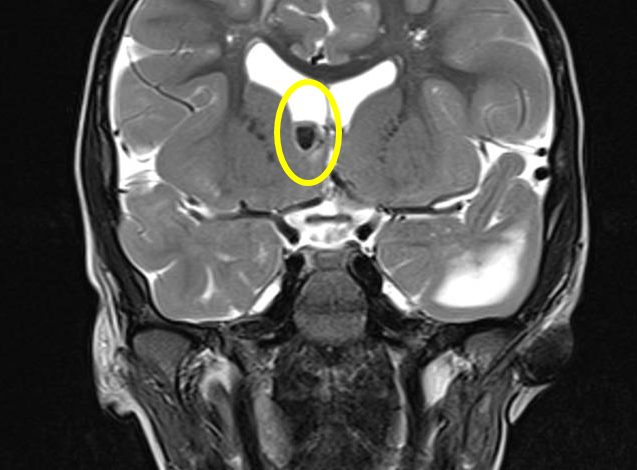

La sclerosi tuberosa è una patologia genetica rara che colpisce un bambino ogni 6.000 nuovi nati. È dovuta all’alterazione di uno dei due geni (TSC1 o TSC2) che contengono le informazioni necessarie per produrre le proteine che contribuiscono a impedire lo sviluppo di tumori. Questa malattia, infatti, è caratterizzata dalla formazione di tumori benigni multipli (amartomi) localizzati prevalentemente a livello cerebrale, renale, cardiaco, polmonare e cutaneo. Le manifestazioni cliniche variano da soggetto a soggetto; nei casi più complessi possono portare a disabilità gravi, impattando notevolmente sulla qualità di vita dei bambini e delle loro famiglie.